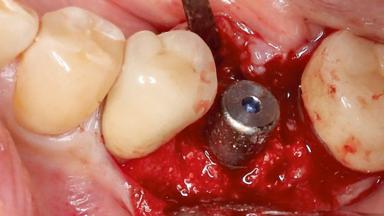

A 70-year-old female patient was referred by her general dentist to the periodontist for assessment and management of an infection associated with implant 36. The general dentist had noted suppuration on probing during examination.